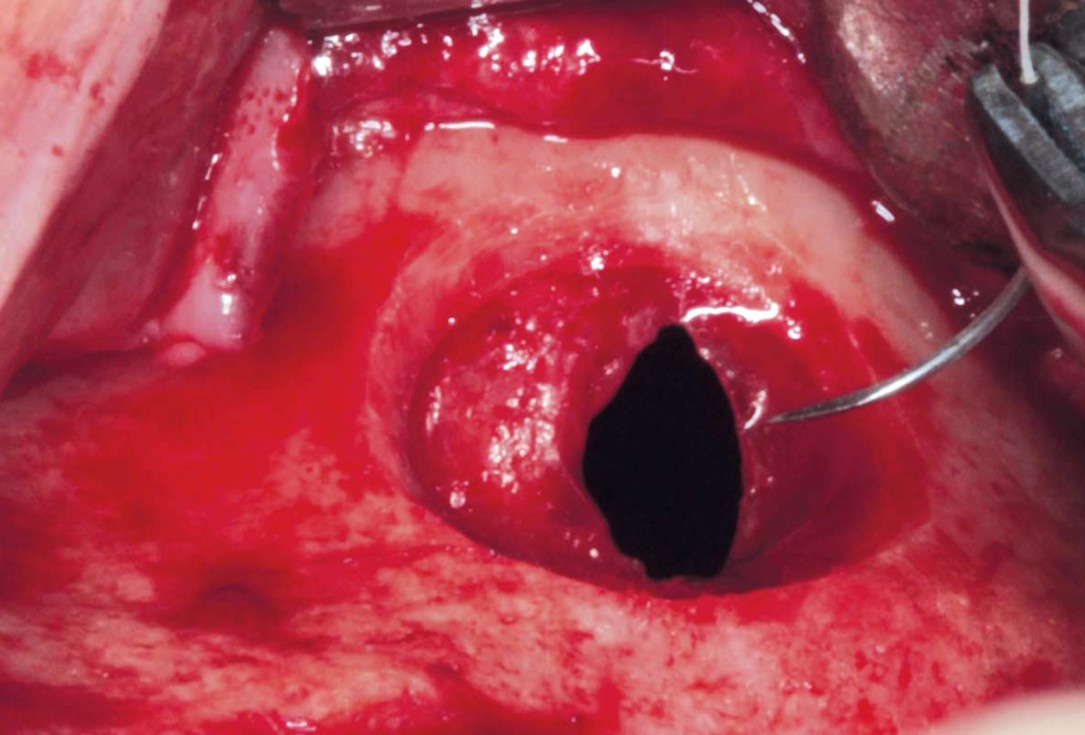

04/35 - Preparation of the lateral sinus window using piezosurgeryMaxillary sinus cyst removal using the Crocodile Technique and subsequent lateral sinus lift - Dres. C. Scognamiglio and A. Perucchi